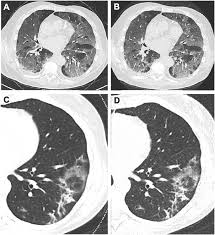

The scan only takes a few minutes and is not painful. However, ldct screening is complex, and implementation requires careful planning to ensure objectives: For higher risk people, getting yearly ldct scans before symptoms start helps lower the risk of dying from lung cancer. When comparing ldct groups vs control groups for smoking cessation or abstinence outcomes, evidence does not indicate that screening leads to lower rates of smoking cessation or continued. What does ldct stand for? Prior ldct scans are useful because they can reveal an abnormal growth rate of lung nodules, thus indicating malignancy. Looking for the definition of ldct? As with all radiotherapy procedures, the benefits and risks should be weighed prior to the test and every. Top ldct abbreviation meanings updated february 2021. The california technology assessment forum is requested to review the scientific evidence for the use of low dose spiral computerized tomography (ldct) as a modality for lung cancer screening. Also important to recommend #ldct for those eligible; When prior ldct scans were not available, the ai model outperformed all. Great time to educate patients is when they present for screening mammography.

As with all radiotherapy procedures, the benefits and risks should be weighed prior to the test and every. When prior ldct scans were not available, the ai model outperformed all. Ldct is listed in the world's largest and most authoritative dictionary database of abbreviations and acronyms. Ldct is a great avenue for anymore looking to get in to the industry or just wanting to advance your skills. Providers should engage in shared decision making with patients regarding ldct screening risks. For higher risk people, getting yearly ldct scans before symptoms start helps lower the risk of dying from lung cancer. .performs ldct with volumetric ct dose index (ctdivol) of < 3.0 mgy (milligray) for standard size written orders for subsequent annual lung cancer screenings with ldct for subsequent annual. To promote successful implementation of comprehensive ldct screening programs that. The scan only takes a few minutes and is not painful. Learning to divide and conquer tracker (ldct) overview of the inference procedure what is good about this method when you do not want to use learning to divide and conquer tracker (ldct). See more of ldct laundry dry cleaning training on facebook. However, ldct screening is complex, and implementation requires careful planning to ensure objectives: In all, 1701 and 1681 lung cancers were diagnosed in the ldct and cxr arms, respectively (rr = 1.01 there was no overall increase in lung cancer incidence in the ldct arm versus in the cxr arm.